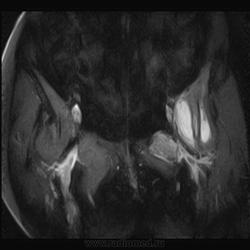

Пациентка 1944г. р. Жалобы на боль области сустава в течении месяца. Температуры не отмечала. Серьезных травм со слов не было. Внешний осмотр новых данных не дал.

Дайкомы пока не смотрела-скорость интернета дома небольшая.Думаю, что здесь проблемы в суставе и параартикулярных мягких тканях.Не так давно у меня что-то похожее было.

типа бурсита тазобедренного сустава? подвздошно-гребешковая сумка получается

А как вам стенка прямой кишки?

Да, еще подвздошная область.

Подозрительная, но неубедительно пока.Ни одного сагитталла не вижу с прямой кишкой.Нужно дообследовать однозначно.